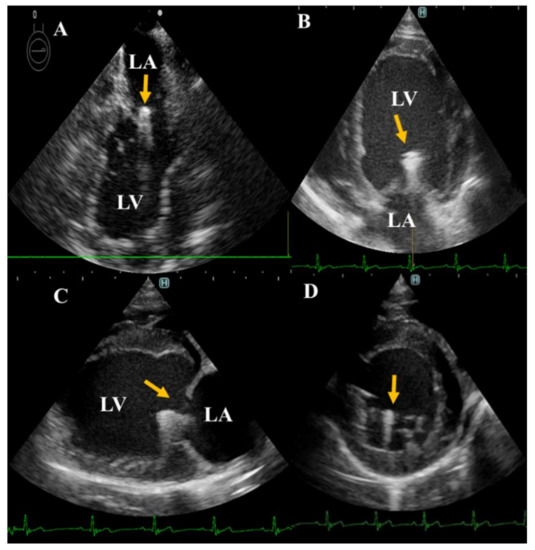

Figure 2. Pulsed-wave Doppler echocardiography for evaluation of the mitral inflow from left apical four-chamber view after TEER implantation. Increase in E wave values was observed after TEER implantation. eV, early diastolic filling velocity; aV, atrial filling velocity.

The detailed echocardiographic parameters are listed in Table 1. The left ventricular dimensions showed no dramatic changes after the surgeries. The fractional shortening was increased postoperatively in both dogs compared with the baseline, but this increase was much higher in dog 2. The mitral inflow velocity waves (E and A) were significantly increased after the operation and throughout the investigation period (Figure 2). The mitral valve orifice in both dogs was slightly narrowed after the operations (2–3 mm difference) at the second and third weeks. In addition, the stenosis was not progressive and both dogs showed slight enhancement of the mitral orifice at the fourth week. Concomitantly, the LA/Ao, early diastolic inflow to myocardial velocity (E/e’), and mitral valve regurgitation velocity (MR) were increased in both dogs after surgery.

E- and A-waves have been reported to serve as indicators of increased left ventricle filling pressures and diastolic dysfunction, respectively [1]. The prediction of postoperative echocardiographic changes in normal dogs will offer important information regarding the evaluation of postoperative hemodynamic changes. In the present report, the postoperative E wave was higher than the preoperative measurement, likely caused by the decreased mitral orifice area following the device placement. The E wave is sometimes used for the estimation of atrial pressure; however, the E wave can be affected by multiple factors, including preload, diastolic function, and others [18,27].